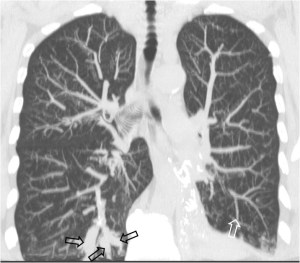

SIGNO DE LA PLEURA DESPEGADA o DIVISIÓN PLEURAL

Es un signo de empiema en la TC de tórax con contraste intravenoso. El signo consiste en el despegamiento de ambas hojas pleurales, que muestran un engrosamiento liso difuso y un realce con la administración de contraste. La imagen muestra la pleura visceral (flecha superior) y la pleura parietal (flecha inferior) despegadas. Ambas hojas se unen en los márgenes de la colección.

Otro ejemplo de este signo. El empiema muestra el despegamiento de las hojas pleurales visceral y parietal (flechas negras). Además, puede verse gas dentro del empiema (flecha blanca) y pulmón colapsado adyacente a la colección (flecha roja).